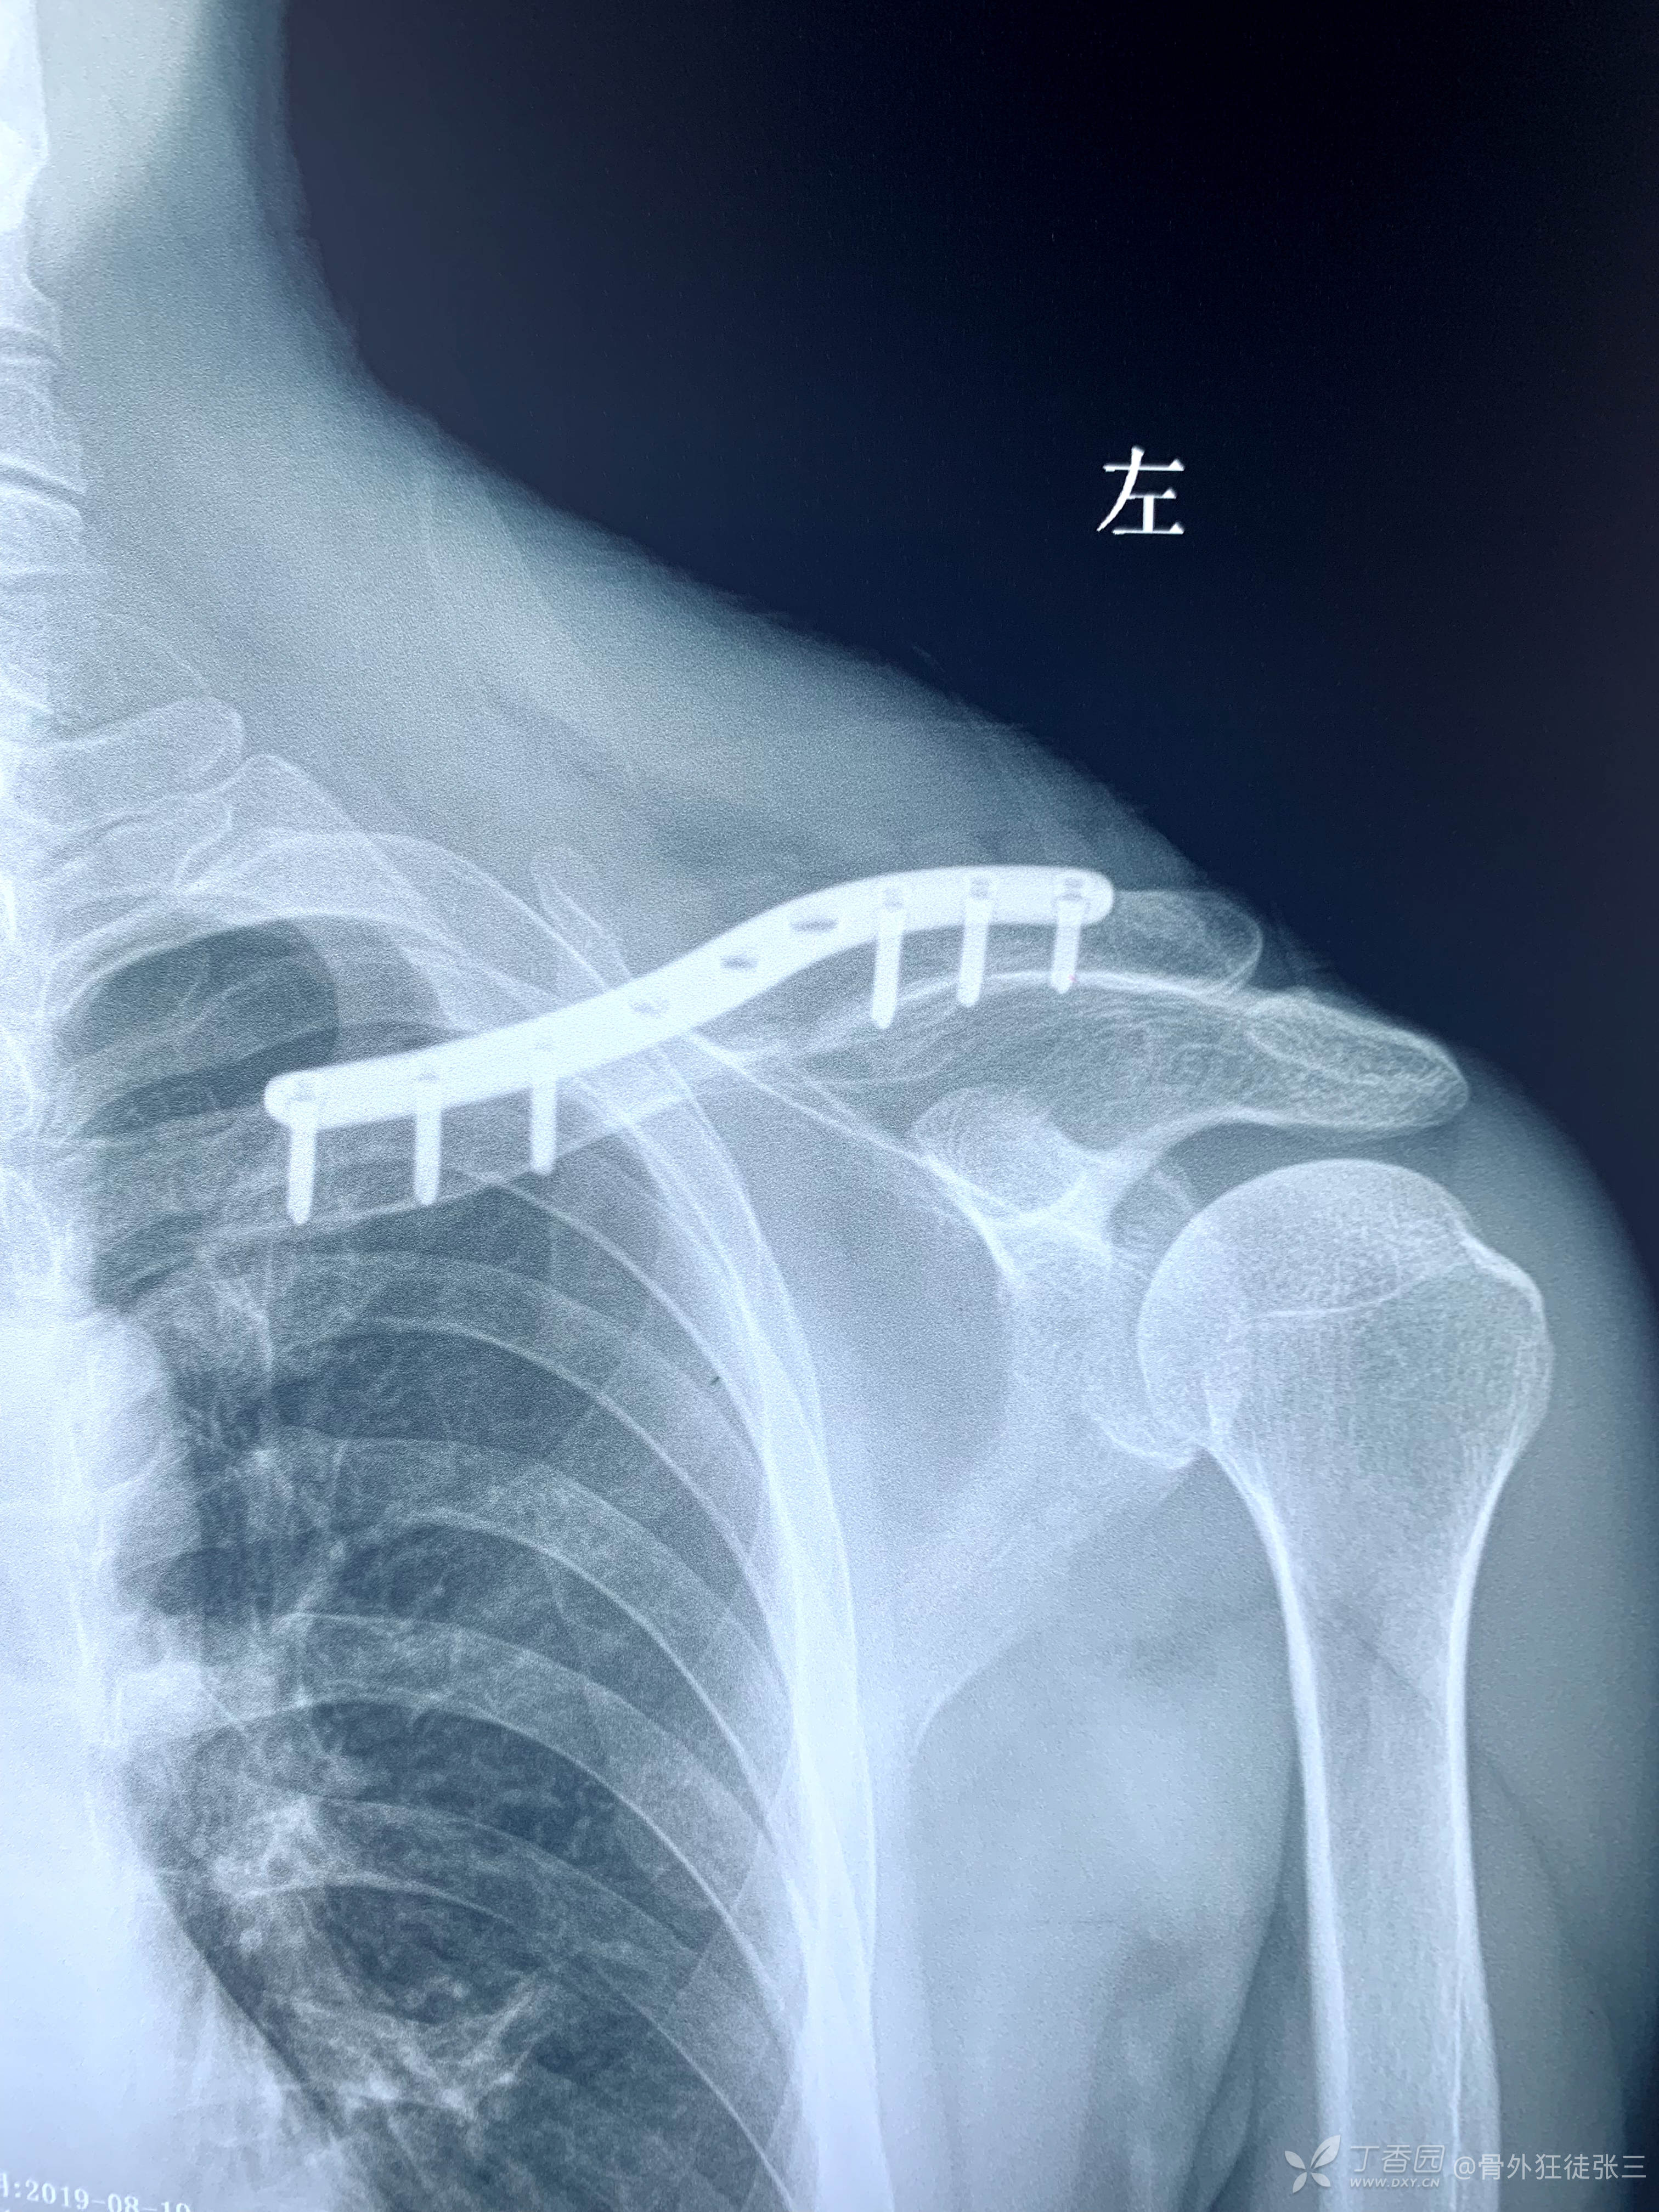

患者:女

年龄:52岁

主诉:左锁骨骨折术后皮肤感觉异常、肩关节活动障碍4月。

简要病史:4月前因“左锁骨骨折”在外院行切开复位内固定术,术后患者即感到切口胸前肩关节前侧区域皮肤感觉麻木不适,上臂悬吊4周后开始肩关节功能障碍。现麻木区域减小,肩关节疼痛活动障碍。为求治疗,来诊。

骨折愈合良好